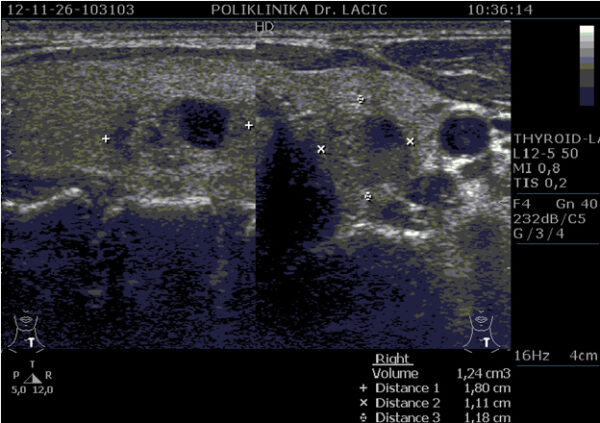

Ultrazvuk je morfološka pretraga koja koristi ultrazvučne valove za prikaz štitnjače. Ovom pretragom analiziramo građu i veličinu štitnjače, te otkrivamo eventualno prisutne morfološke promjene u štitnjači, kao što su čvorovi (kvržice), ciste, upalne promjene, te mjerimo veličine istih. Pomoću ultrazvuka uvijek je potrebno pregledati vrat i pripadajuće limfne čvorove čije povećanje može biti vezano za bolesti štitnjače.

U sklopu Centra za štitnjaču Poliklinike Lacić nabavljen je najnoviji američki ultrazvučni aparat sa color Dopplerom Philips Affiniti 70, koji je opremljen jedinstvenim „PureWave“ ultrazvučnim sondama. Tehnologija izrade tzv. „single crystal“ ili „PureWave“ ultrazvučnih sondi omogućuje duboku penetraciju što omogućuje bolju vizualizaciju štitnjače i svih struktura vrata. Philips Affiniti 70 ultrazvučni sustav je jedini sustav u klasi koji može koristiti „single crystal“ ili „PureWave“ tehnologiju. Čisti, uniformni „PureWave“ kristali imaju 85% bolju učinkovitost prilikom emitiranja i primanja ultrazvučnih zraka nego klasični piezoelektrični materijali. Ova izuzetna tehnologija omogućuje naprednu penetraciju uz izvrsnu rezoluciju u dubljim dijelovima slike, čime se postiže vrhunski prikaz štitnjače i svih struktura vrata. Time se omogućuje još točnije mjerenje svih morfoloških kao i hemodinamskih parametara. Na taj način smo u mogućnosti još ranije otkrivati bolesti štitnjače a samim time ih onda i bolje liječiti.